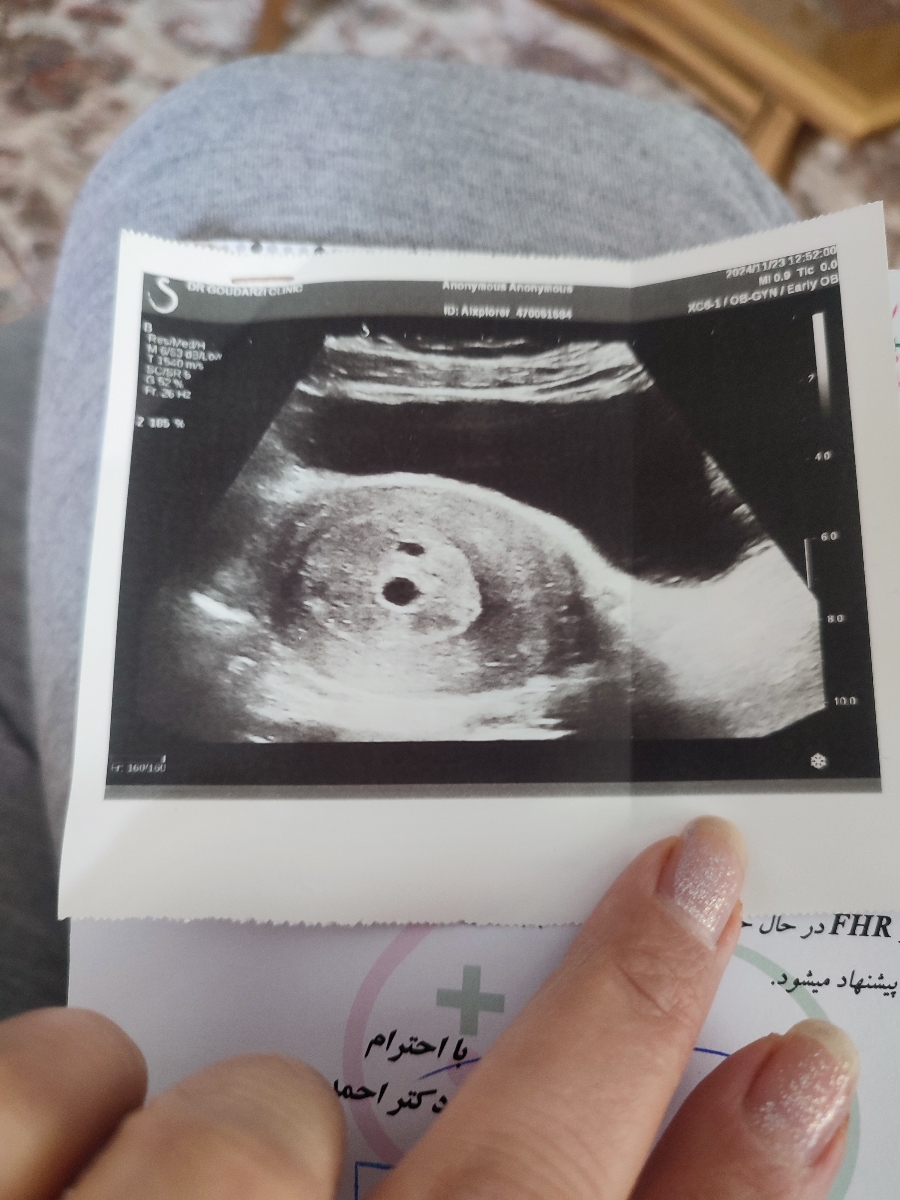

سلام وقتتون بخیر ببخشید من امروز باید ۷ هفته و دو روزم باشه رفتم سونوگرافی گفت که توی ۵ هفته و ۵ روز سن بارداریت مونده در حالی که وقتی که ۵ هفته و ۵ روز بودم 7msd میل بوده امروز شده ۱۰ میل پس چرا گفته که رشد نکرده و حتی گفته که که فتال پل مشاهده نشده در حالی که سونو قبلی مشاهده شده بود به نظر شما سونو درست تشخیص داده شده یا نه من باید چیکار کنم.از هماتوم چیزی نگفت یعنی ندید یا جذب شد به نظر شما به خاطر مثانهام که زیادی پر بود تشخیص اشتباه نبود؟

پزشک اوما

عکس گزارش سونوگرافی را ارسال کنید تا ببینم

سلام وقتتون بخیر ببخشید سونو قبلی و سونو جدید رو فرستادم